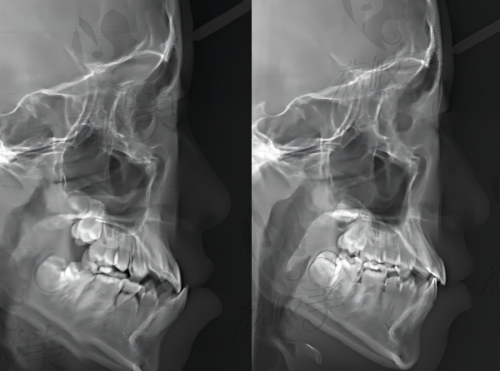

专精的医生团队:友睦口腔的医生大多具备丰富的临床经验和扎实的专精知识。他们在牙齿正畸、牙齿种植、口腔修复等多个领域深入研究,拥有不错的技术。以牙齿正畸为例,医生们能够根据患者的牙齿状况和面部特征,制定个性化的矫正方案,不仅能改善牙齿排列不齐的问题,还能提升面部美观度。在牙齿种植方面,医生们熟练掌握精良的种植技术,确保种植体的稳定性和成功几率,为缺失牙患者带来良好的咀嚼体验。

精良的诊疗设备:医院注重 医疗品质,引进了精良的口腔诊疗设备。这些设备能够为患者提供精细、效率高的诊断和治疗方案。例如,数字化口腔扫描仪可以快速、正确地获取患者牙齿的三维模型,医生通过模型可以更直观地了解患者的牙齿情况,制定更科学的治疗计划。

项目点评:友睦口腔的牙齿正畸项目价格相对合理,根据不同的矫正方式,价格有所差异。传统金属矫正价格较为亲民,适合预算有限的患者;隐形矫正则更加美观舒适,但价格相对较高。牙齿种植项目,根据种植体的品牌和型号不同,价格也有所不同。医生会根据患者的具体情况,推荐合适的种植体,确保患者获得满意的治疗成效。